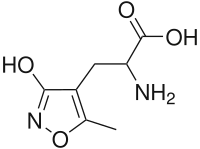

- Peyote (mescaline)